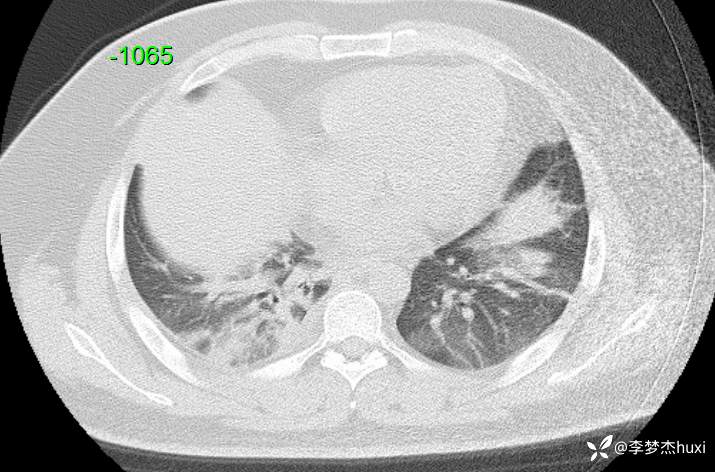

【现病史及既往史】: 1.患者青年 男,患者缘于2天前无诱因出现胸痛,为前胸痛,伴后背疼痛,咳嗽及深呼吸时明显,伴咳嗽,痰不易咳出,伴恶心、呕吐,伴发热,体温最高达37.7℃,无寒战,无咯血,院外未应用药物治疗,症状无明显好转,为求进一步治疗来院就诊,门诊查胸部CT提示:双肺炎症,较前进展,双肺纹理增重,右肺实性结节,建议随诊复查,双侧胸膜局部增厚,右侧胸腔少量积液。以“肺炎”收住院;。

【检查】: 4.辅助检查:心电图示:窦性心动过速,门诊查胸部CT提示:双肺炎症,较前进展,双肺纹理增重,右肺实性结节,建议随诊复查,双侧胸膜局部增厚,右侧胸腔少量积液。

【临床诊断】: 社区获得性肺炎,非重症。

【治疗经过及结果】:莫西沙星抗感染